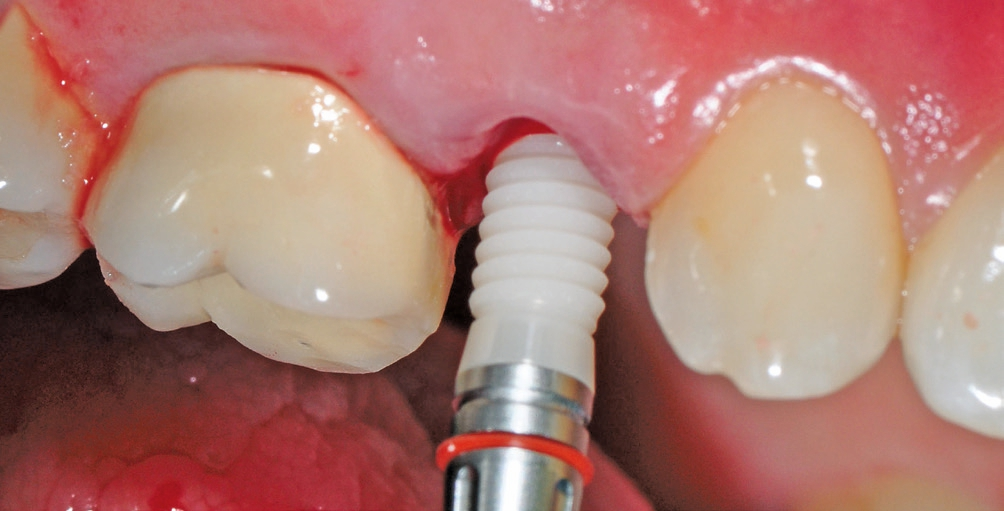

Implantatinsertion

Nach sorgfältiger Kürettage und Inspektion einer idealen Knochenalveole vom Typ I [11] konnte mit der Sofortimplantation begonnen werden. Die ersten beiden Pilotbohrungen wurden teilnavigiert mit der Bohrschablone durchgeführt. Das restliche Bohrprotokoll wurde nach den Vorgaben des Herstellers frei durchgeführt. Mit der Insertion des Implantats konnte die nötige Primärstabilität von 35 Ncm für eine sofortige provisorische Versorgung erreicht werden. Im Vorfeld war ein Situationsmodell der Ausgangssituation und darauf eine Tiefziehschiene vorbereitet worden, die jetzt für die intraorale Herstellung des Provisoriums mit fließfähigem Kompositmaterial verwendet wurde. Als stabilisierende Gerüststruktur diente dabei die präzise sitzende Einbringkappe (insertion.transfer) auf dem Implantatkopf, die zuvor auf die entsprechende Höhe eingekürzt worden war. Nach der Ausarbeitung und okklusalen Adjustierung der Krone wurde diese provisorisch zementiert.